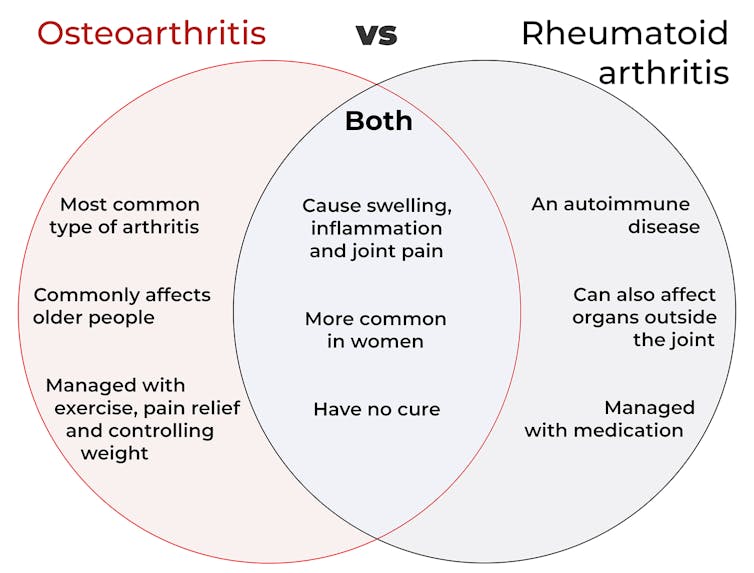

The two most common types, osteoarthritis and rheumatoid arthritis, can both cause joint pain, swelling and stiffness. Both are more common in women. Neither can be cured.

But their causes, risk factors and treatments are different – here’s what you need to know.

Osteoarthritis is the most common form of arthritis. It affects 2.1 million Australians, mostly older people. About a third of Australians aged 75 and older have the condition.

Unlike osteoarthritis, rheumatoid arthritis is an autoimmune disease. This means the immune system attacks the joint lining, causing inflammation and damage.

Rheumatoid arthritis is less common than osteoarthritis, affecting around 514,000 Australians. It mostly impacts the wrists and small joints in the hands and feet, though larger joints such as the elbows, shoulders, knees and ankles can also be involved.

It can also affect other organs, including the skin, lungs, eyes, heart and blood vessels. Fortunately, disease outside the joint has become less common in recent years, likely due to better and earlier treatment.

No treatment can stop osteoarthritis progressing. However many people manage their symptoms well with advice from their doctor and self-care. Exercise, weight management and pain medicines can help.

Treatments for rheumatoid arthritis focus on preventing joint damage and reducing inflammation.